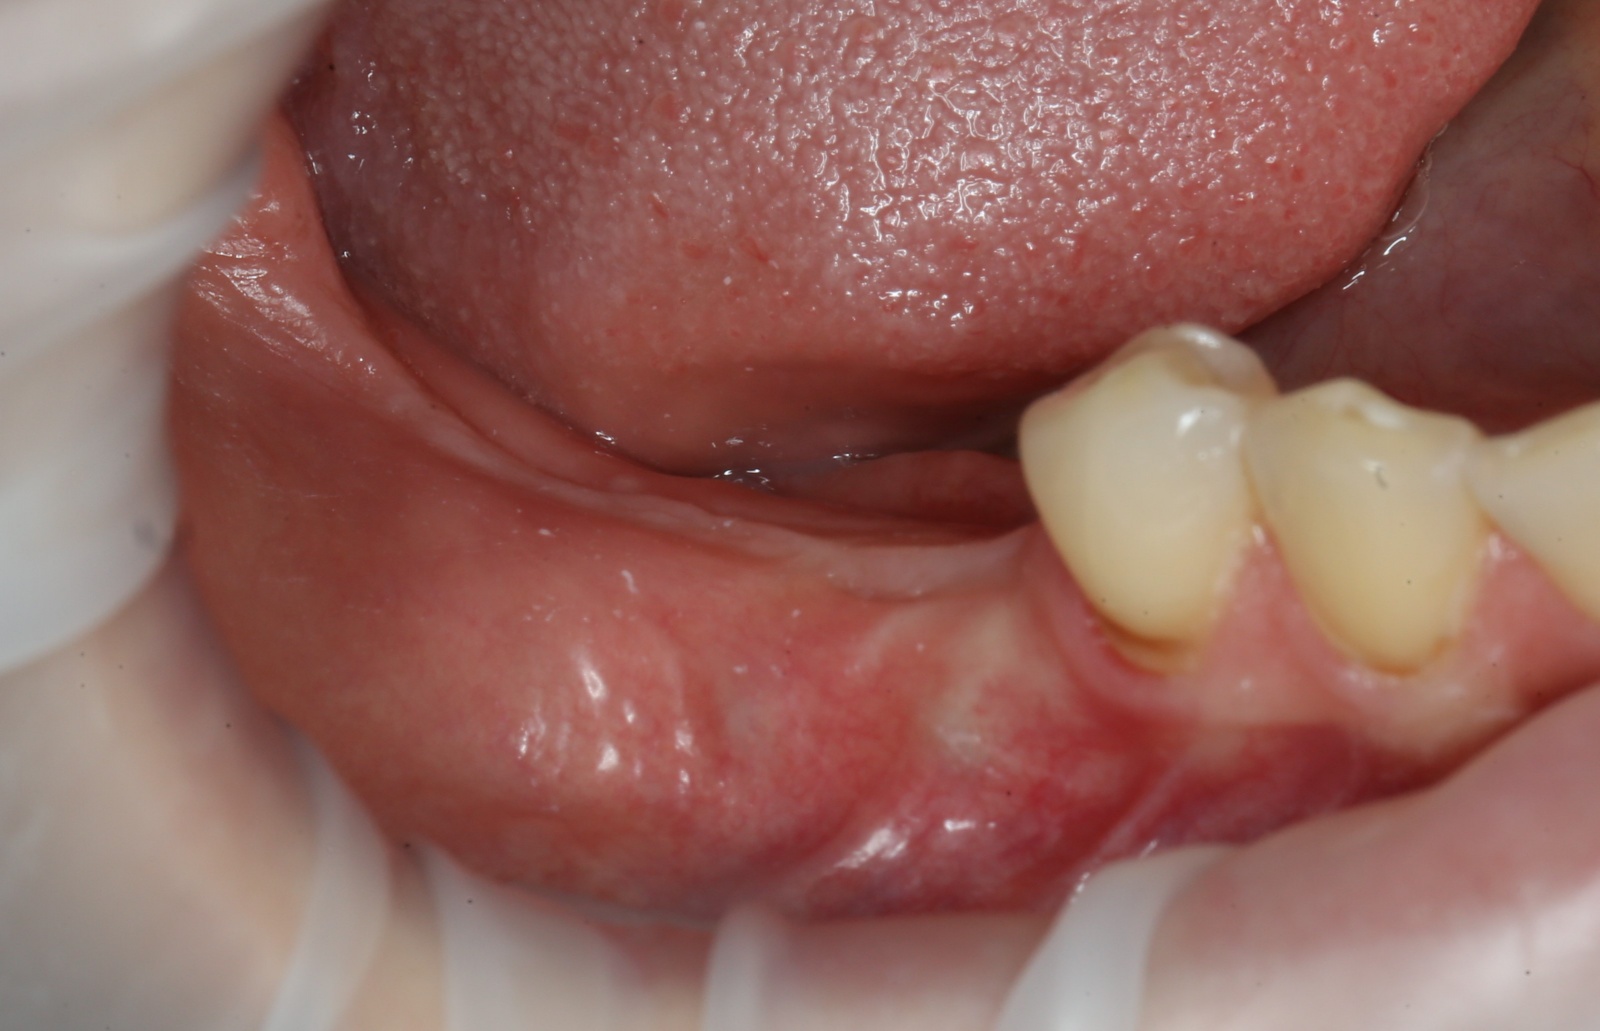

Итак, 5 месяцев позади:

Всё тот же разрез и скелетирование кости: